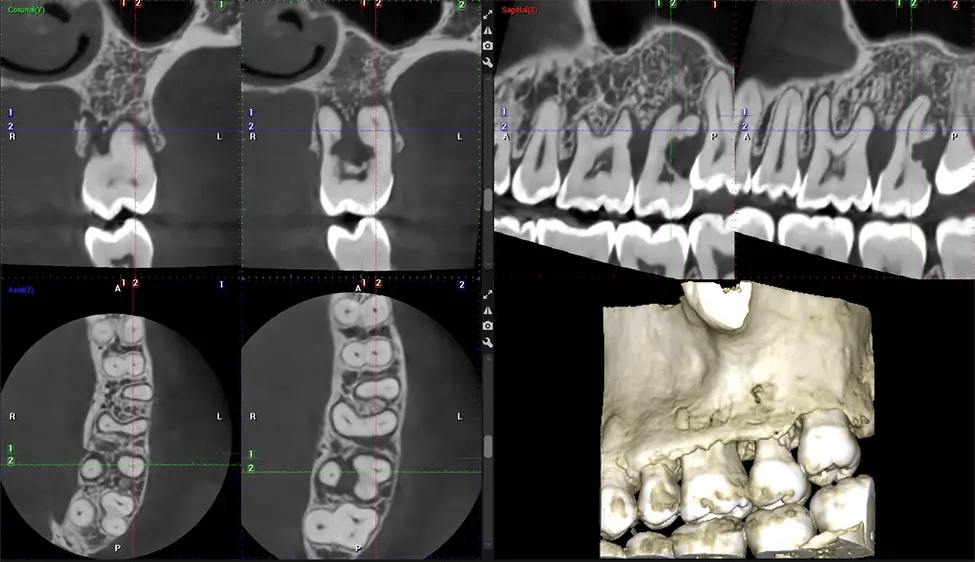

Cone Beam Computed Tomography (CBCT) is an advanced imaging technique used in dentistry and maxillofacial surgery to obtain detailed 3D images of the oral and maxillofacial structures. At Dr G Dental Studio, our CBCT scanners utilize a cone-shaped X-ray beam and a specialized detector to capture images from different angles. A computer then combines these images to create a 3D representation of the patient’s oral anatomy.

This 3D scan, called cone beam computed tomography, gives your dentist a more complete image of your oral anatomy and disease processes than a traditional X-ray. Unlike conventional X-rays, which capture a 2D image of your mouth from various angles, a 3D scan takes multiple digital X-rays for one image. It provides a complete view of your jaw, teeth, nerves, and soft tissues. This enhanced view allows dentists to detect minor issues not visible in traditional 2D scans, such as impacted wisdom teeth or bone fractures in the sinus cavity.

There are many benefits to using CBCT technology, especially compared to the traditional 2D X-ray format. One of the most significant advantages of CBCT scans is that they provide much more information than traditional X-rays. A scan lets your dentist see images from all angles of your jaw and mouth, including your sinuses, nasal cavity, cheekbones, and other surrounding areas. This added information helps your dentist craft a comprehensive treatment plan that addresses all aspects of your oral health.

Another significant benefit is that 3D imaging provides more precise images of your bone structure. These images are more detailed, providing you with a more accurate diagnosis. An accurate diagnosis means better treatment for you.